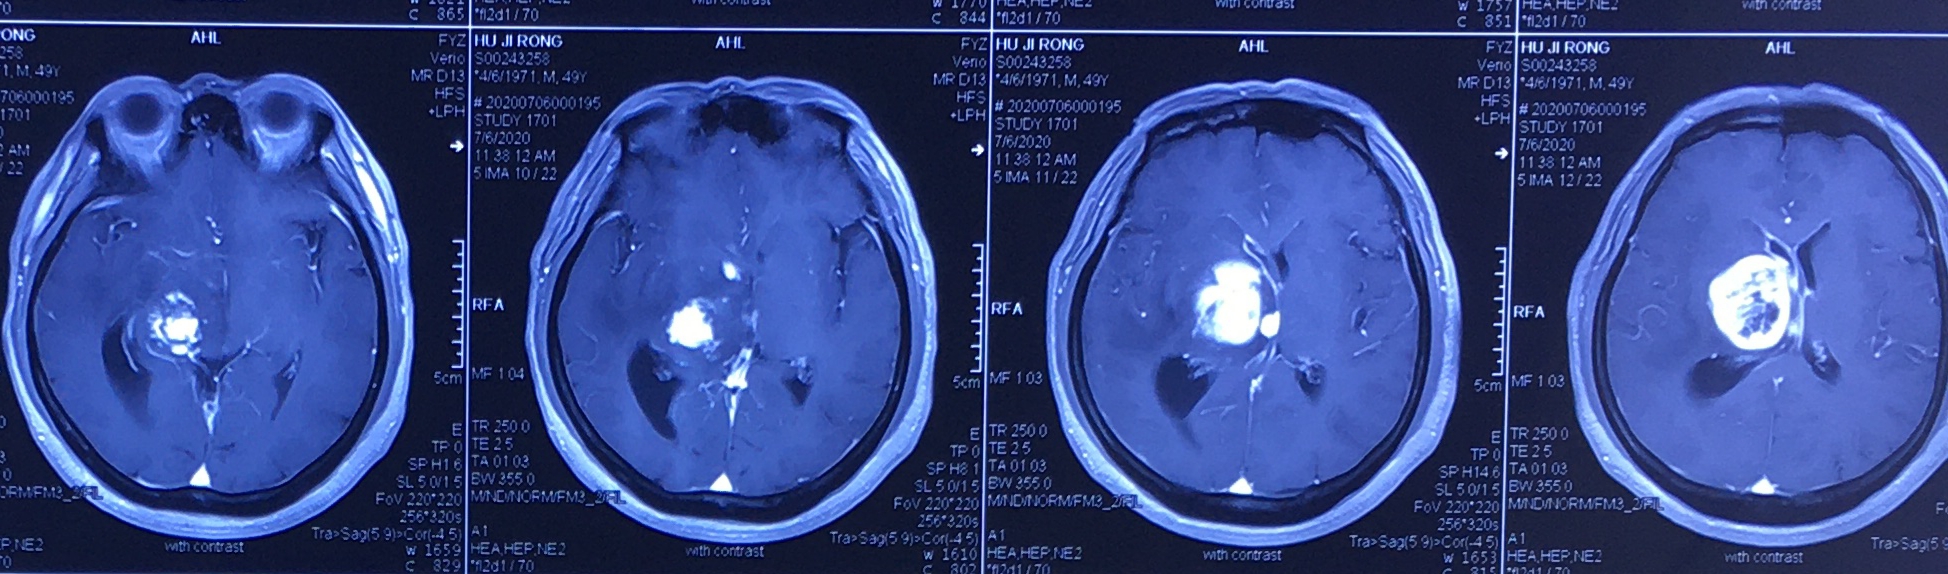

病例 (术前) 49岁的胡某,因头部昏沉不适3个月到我院神经外科就诊,颅脑MRI显示右侧丘脑占位性病变,病变性质不明。考虑到患者仅四十多岁,病灶位于重要功能区,开颅手术切除术后偏瘫风险极大。神经外科团队精确规划设计路径和靶点,安装立体定向头架后,于7月9日全麻下行立体定向脑内病灶活检术。 (术前规划设计路径和靶点) 术中按照术前规划的路径及靶点,顺利取出病变组织,术中快速冰冻病理显示为恶性肿瘤,术后送常规病理及免疫组化进一步确诊及分类。术后复查颅脑CT显示无明显出血,患者病情稳定,肢体感觉运动正常。术后第二天即下床活动。 (术中利用活检针取材) 病理诊断是脑内病灶定性诊断的金标准。立体定向活检术是明确颅内深部病变组织病理学诊断的安全、有效方法;由于立体定向三维靶点定位的误差范围在1.0mm以内,定向活检既可以补充影像技术对病变定性诊断的不足,又避免了开颅手术导致神经功能损害,而且定位准确,创伤小,安全可靠,并发症少,病人痛苦小,医疗费用低。 它不仅可提供可靠的病理学依据、达到定性诊断的目的,还可以同期配合后续治疗(肿瘤内植入放射性粒子)。立体定向活检术有不同的引导方式,且越来越先进和精细,此项技术包含很多细节和内容,技术含量高。脑立体定向手术还可用于脑出血、帕金森病、癫痫、疼痛、精神性疾病的精准手术治疗。